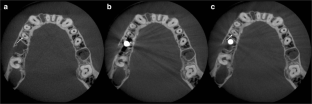

Fig. 2